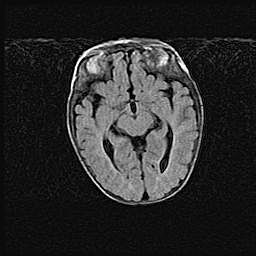

Открытая гидроцефалия.

Возраст: 9 месяцев 12 дней

Вес: 6800 г

Пол: мужской

Окружность головы: 41,5 см

Срок гестации: 28 недель

Гидроцефалия головного мозга у новорожденных имеет характерный признак: опережающий рост окружности головы приводит к визуально хорошо определяемой гидроцефальной форме сильно увеличенного в объёме черепа. Детские неврологи определяют следующие симптомы гидроцефалии у грудничков: выбухающий напряжённый родничок, частое запрокидывание головы, смещение глазных яблок к низу.